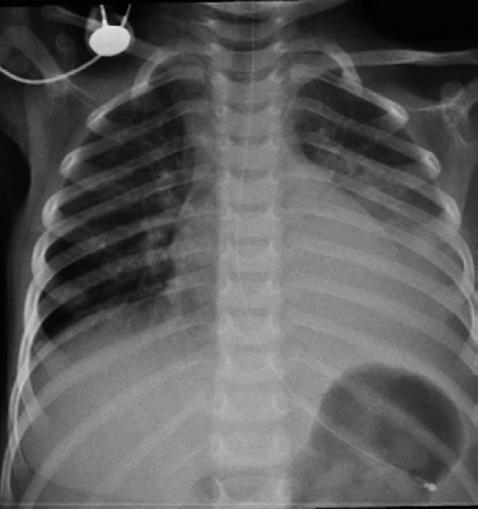

Se confirmará el diagnóstico de pleuroneumonía en la radiografía de tórax (Figura 1), por lo que inició terapia antibacteriana con ceftriaxona.

Figura 1. Radiografía de tórax niño de 2 años, neumonía neumocócica con empiema y síndrome hemolítico urémico (SHU-Sp).